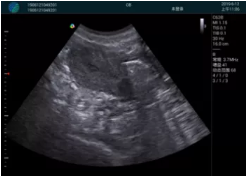

清晰顯示孕囊,通過軟件包計(jì)算孕齡7w+6d

M20實(shí)時(shí)引導(dǎo),術(shù)中清晰顯示孕囊被破壞和抽吸針的過程,清晰顯示吸引針

抽吸結(jié)束后縱切子宮,孕囊已被完全抽吸,未見明顯殘留

橫切子宮,發(fā)現(xiàn)右側(cè)宮腔靠近宮角處有少許脫模樣殘留

M20引導(dǎo)下,抽吸針找到右側(cè)宮角處再次清掃

二次抽吸后再次進(jìn)行超聲檢查,宮腔未見殘留,宮腔線清晰顯示